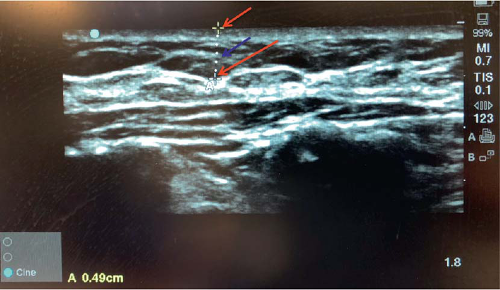

While predicted mastectomy flap thickness can be qualitatively assessed clinically in the preoperative setting based on breast morphology and patient examination, quantitative measurement can be difficult. The increased availability of preoperative breast imaging provides a unique opportunity to review and quantify each patient’s unique breast anatomy. Digital mammography can be utilized for this purpose; however, ultrasonography and magnetic resonance imaging (MRI) are more commonly utilized in our practice (8,12,13).

We believe in an oncoplastic approach to immediate postmastectomy breast reconstruction, relying on cooperative coordination being the ablative and reconstructive teams (14,15). At our institution, a majority of patients will have undergone preoperative MRI for oncologic planning. Therefore, each patient’s preoperative breast MRI can be reviewed by the breast and plastic surgeon. The distance from the breast skin to the breast capsule may be measured at multiple points in both the axial and sagittal planes (Fig. 18-3). This provides a quantitative

estimation of predicted mastectomy flap thicknesses based on each patient’s anatomy. Prior to infiltration of any dilute lidocaine with epinephrine solution in the operating room, hand-held ultrasonography may be utilized to confirm these estimated thicknesses using a second imaging modality in roughly the same locations as those measured on MRI (Fig. 18-4). We have found that this aids in the identification of the breast capsule intraoperatively, facilitating an anatomic mastectomy flap dissection in the optimal plane.